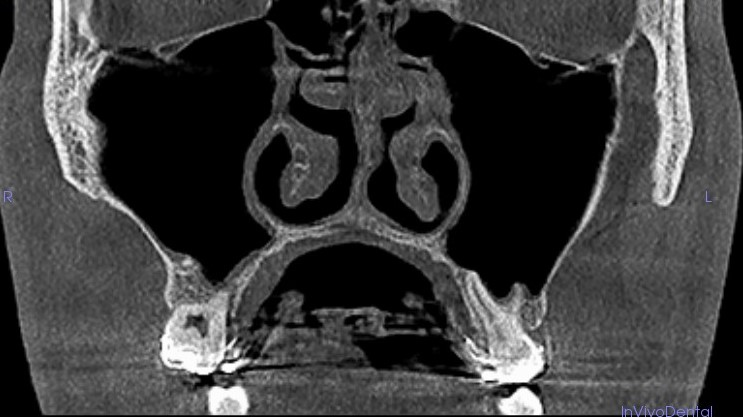

Pacjent po ekspansji szczęki

Pacjent po ekspansji szczęki - zauważalna poprawa drożności przewodów nosowych.